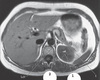

A

Inferior mesenteric artery

IMA

8

Q

1

A

gastroduodenal Artery (fig 7.156)

9

Q

2

A

common hepatic Artery(fig 7.156)

10

Q

3

A

splenic Artery (fig 7.156)